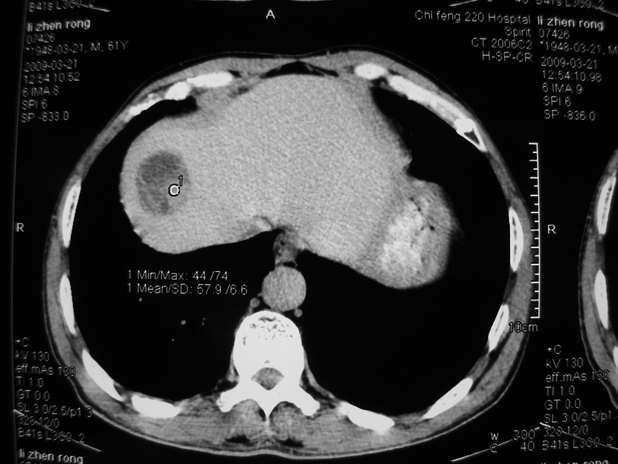

以下是引用余辉在2009-3-21 21:36:00的发言:[br]图像太乱了,建议楼主直接将强化数据按顺序列出来,病灶位置较表浅薄,有肝炎病史,灶内实性成分有显著强化,动脉期约60hu,考虑肝癌可能性大,进一步检查。